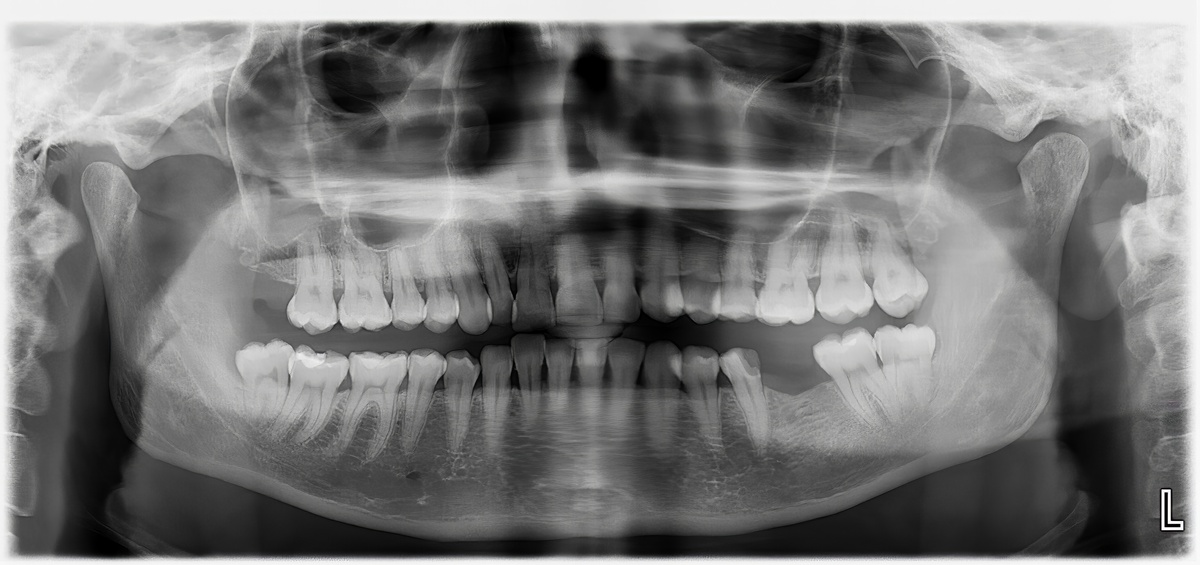

首先,核磁共振成像可以帮助医生更准确地了解患者的口腔结构和牙齿情况,从而制定出更合理的治疗方案。例如,在进行正颌手术前,医生需要了解患者的颌骨结构、牙齿位置和咬合情况等信息,以确定手术的具体步骤和效果。而通过核磁共振成像,医生可以清晰地看到这些信息,从而更加精准地进行手术。

其次,核磁共振成像还可以帮助医生观察患者的牙齿移动情况,以及矫正器对牙齿的影响。这对于一些难度较大的矫正情况尤为重要。例如,对于一些牙齿移动较为复杂的患者,医生需要通过矫正器的调整,来逐步调整牙齿的位置和咬合情况。而通过核磁共振成像,医生可以直观地观察到牙齿的移动情况,从而及时调整矫正器的力度和方向,以达到更好的治疗效果。